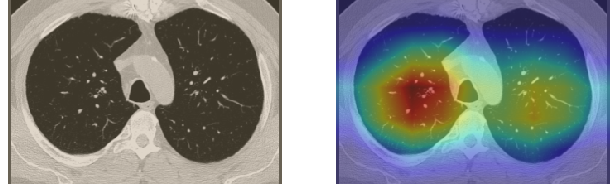

In order to make our models more transparent and provide detailed visual analysis, we present the Grad-CAM localization maps obtained by different models. We consider CT images with COVID-19 abnormalities from the test set of each dataset and highlight the important regions considered for the prediction. For the SARS-CoV-2 dataset we use the Inception V3 model. Figure 13 shows the original CT images and their localization maps. Our model is capable to detect regions that show abnormalities in the CT scans.

In a similar way, we consider classifying the test CT scans from the COVID-19 dataset by the DenseNet169 model and highlight the important regions considered for predictions. We present the original CT images and their localization maps in Figure 13. We can also see that our model is capable to detect the COVID-19 related regions as marked (small square in some images) by expert radiologists.

A wide variety of typical and atypical CT abnormalities have been reported for COVID-19 patients in various studies [58, 59]. So, we tested our models on external CT images extracted from these two publications as they feature typical findings of COVID-19 pneumonia marked by specialists. In order to make sure that not any of the extracted images are unintentionally included in our datasets, specifically the COVID19-CT dataset, we use the model trained on the SARS-CoV-2 dataset. First, the InceptionV3 model is employed to classify the extracted CT images. The model is able to correctly classify the given CT images as COVID-19. Second, in order to interpret the model’s generalization capabilities, we apply the Grad-CAM technique to visualize the regions of abnormalities that are considered. By assessing the different CT images in Figure 15, we can see that the model accurately localizes the disease-related regions. Even more interesting is the fact that the model ignores any specific marks in the images like letters and only localizes the COVID-19 related regions. These visual explanations show the success of our models to learn relevant, generic visual features related to COVID-19 and are capable to correctly classify CT images outside the datasets on which they are trained.